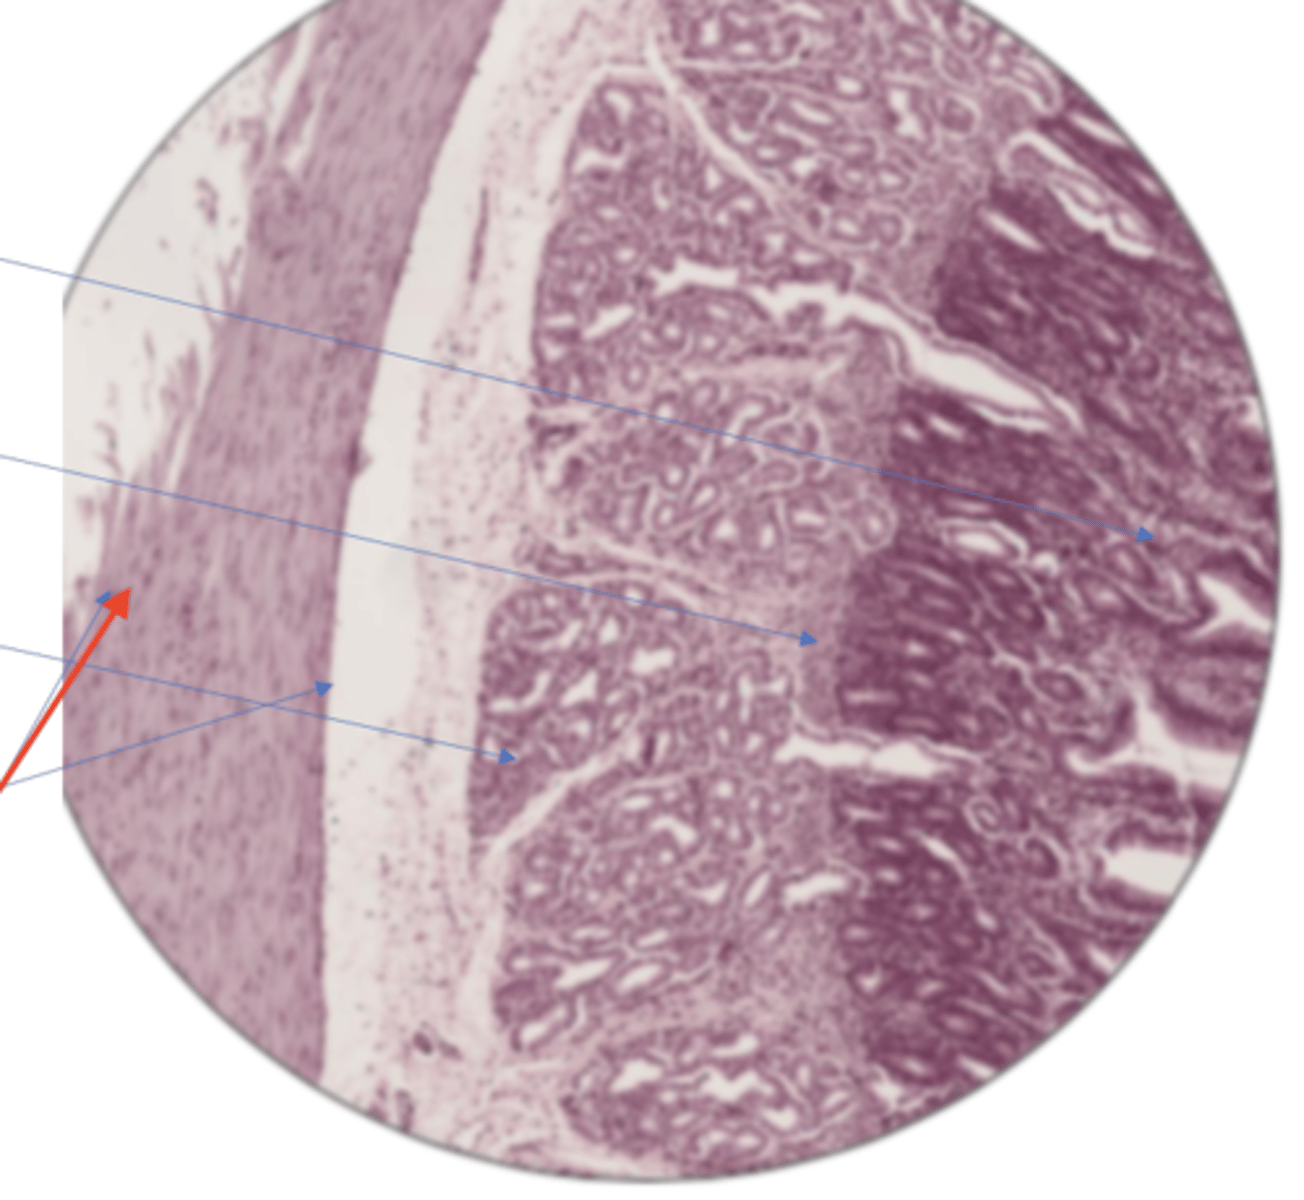

LI mucosa layer (100)

LI mucosa layer (400)